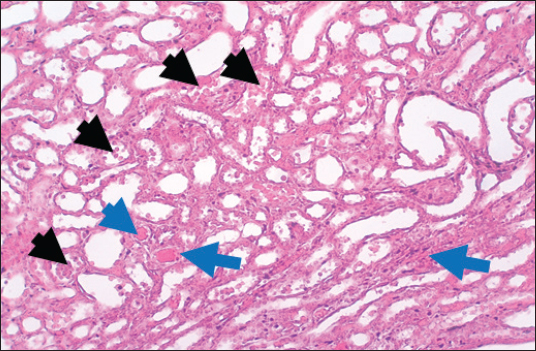

In the control group, histological analysis of kidney sections revealed intact glomeruli and renal tubules (Fig. 1). Conversely, Figure 2 presents a kidney section from the green tea group, which exhibited normal renal tubular epithelial cells, a well-preserved tubular lumen, and an overall normal tubular texture, although some glomeruli showed mild atrophy. The renal section of gentamicin showed atrophy of the glomerular tuft, expansion of the globular space, and significant hyperemia lesions in some glomeruli associated with substantial damage to the superficial cell layer (epithelial cells) in the proximal renal tubules, resulting in a reduction of the tubular lumen space (Fig. 3). In contrast, kidney sections from the gentamicin group that received green tea treatment revealed a marked reveal of both glomeruli and renal tubular epithelium, which appeared normal (Fig. 4 and Fig. 5).

Fig. 2. Rat kidney treated with green tea extract the section shows normal renal tubular epithelial cells with normal tubular lumen (Black arrows), normal tubular texture, and mild atrophy can be seen in some glomeruli (Blue arrows). H and E (10X).

Fig. 4. Kidney of treatment group. The section shows severe hemorrhage (RBCS accumulation in the proximal renal tubules, Black arrows) with ahyperemic lesion in the section of renal tubules (Blue arrows).H and E (10X).